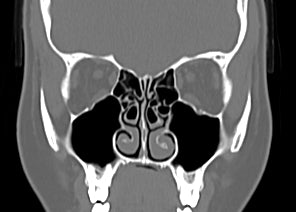

Problemy anatomiczne, które utrudniają prawidłowe oddychanie nosem

Poznaj cztery najczęstsze przyczyny problemów z oddychaniem nosem i dowiedz się, jak proste, nieinwazyjne rozwiązania mogą pomóc wrócić do naturalnego oddechu.